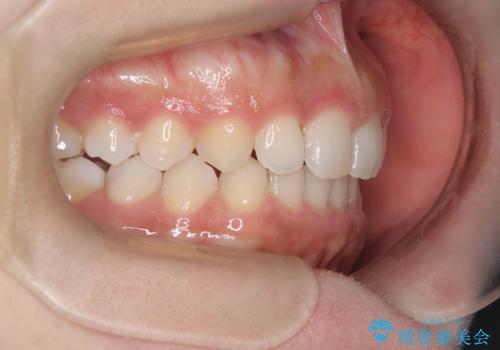

インビザラインで整える深い噛み合わせ

- 患者様は、ディープバイト(深い噛み合わせ)と、咬合平面の左下がりが気になるとのことでご来院されました。診断の結果、非抜歯で治療可能と判断し、透明なマウスピース型矯正装置「インビザライン」を用いる方針としました。治療では、歯列全体の調整を行いながら、咬合平面の水平化を重点的に進める計画を立案しました。2年間で計画的にマウスピースを交換し、左右のバランスと噛み合わせの改善を目指しました。

ディープバイトの矯正は、噛み合わせが深くなりがちなため、細心の注意を払いながら進める必要があります。本症例では、奥歯の高さを調整しつつ前歯の噛み合わせを浅くすることで、全体の咬合バランスを整えました。また、咬合平面の左下がりを修正する過程で、歯列に不均等な力がかからないよう、インビザラインのアタッチメント配置を最適化しました。患者様には装着時間を守っていただき、治療が計画通り進むよう協力をお願いしました。治療終了後には、リテーナーを装着して安定性を確保しました。